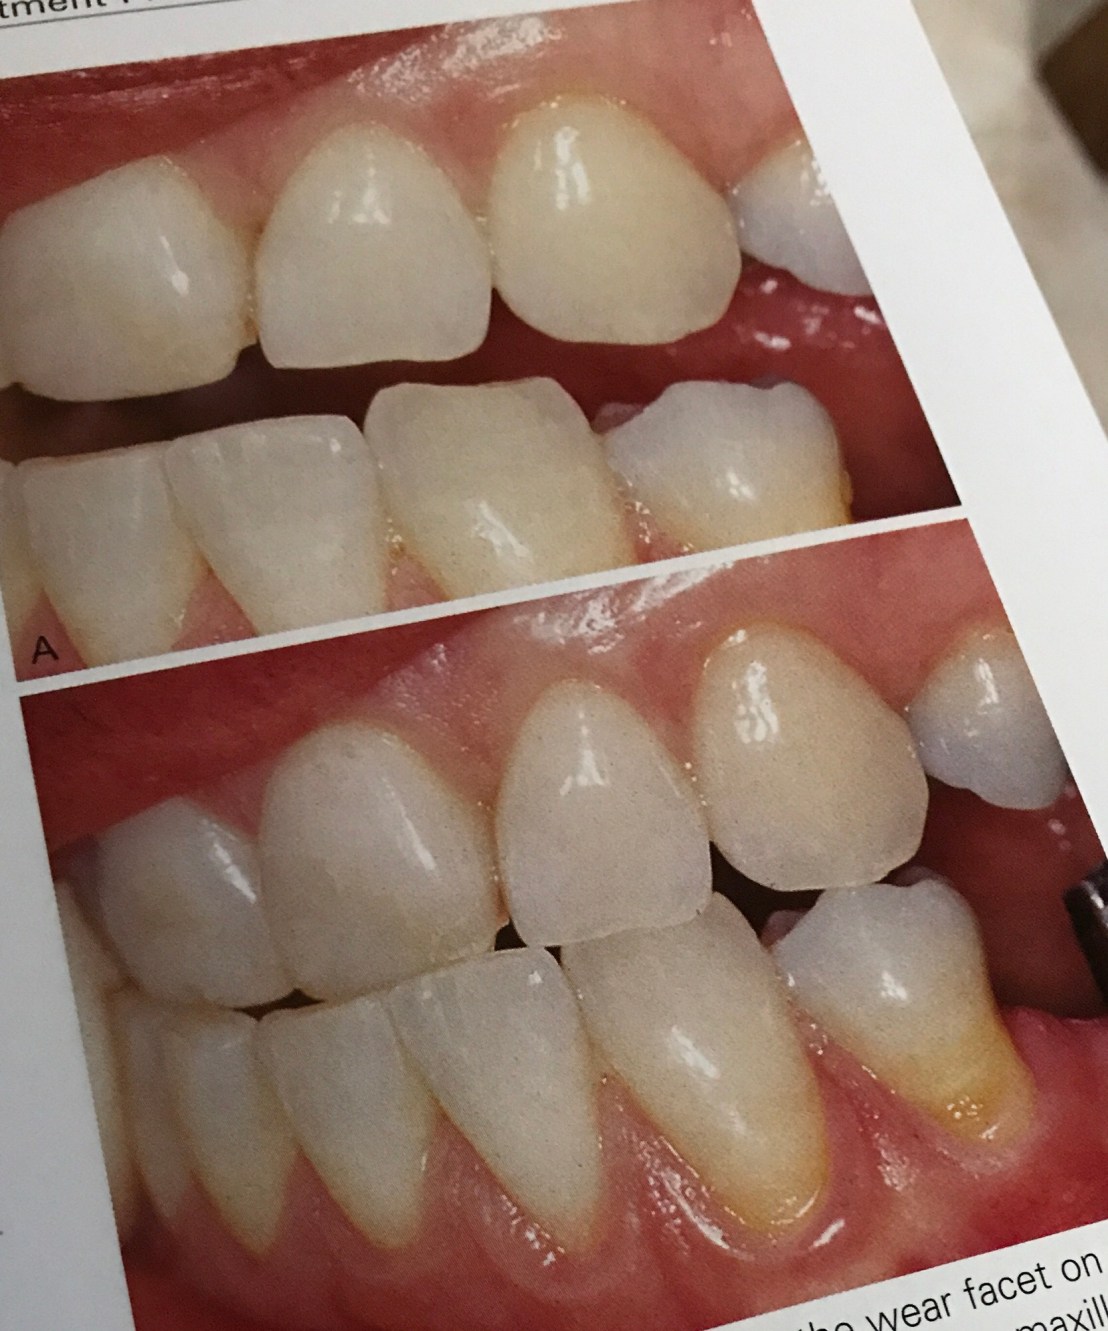

แสดงการสึกของ Canine ล่าง และ notch ที่ฟันคู่สบ 22 –> มี Bruxism

รูปล่าง เวลาทำ Working contact พบ Canine บนสบกับ 34 และสังเกตว่า คอฟันซี่ 34 เกิด abfraction–> แสดงถึง Parafunction

ดังนั้นเวลาที่เราต้องทำ Pros ในฟันหลัง จะต้องปรับแต่งการสบฟัน ไม่ให้เกิดลักษณะนี้ด้วย

ในคนไข้ที่มีฟันหน้าล่างสึก (Bruxism) แบบนี้ เราต้อง restore ฟันหน้าล่างขึ้นมาก่อน เพื่อให้เกิด Anterior guidance ที่ปกติ จึงจะสร้าง Prosthesis ในฟันหลังได้ (หมายความว่า ถ้าเราสร้าง Pros ขึ้นมาโดยไม่สนตำแหน่งฟันหน้า Pros จะ failure ไปด้วย)